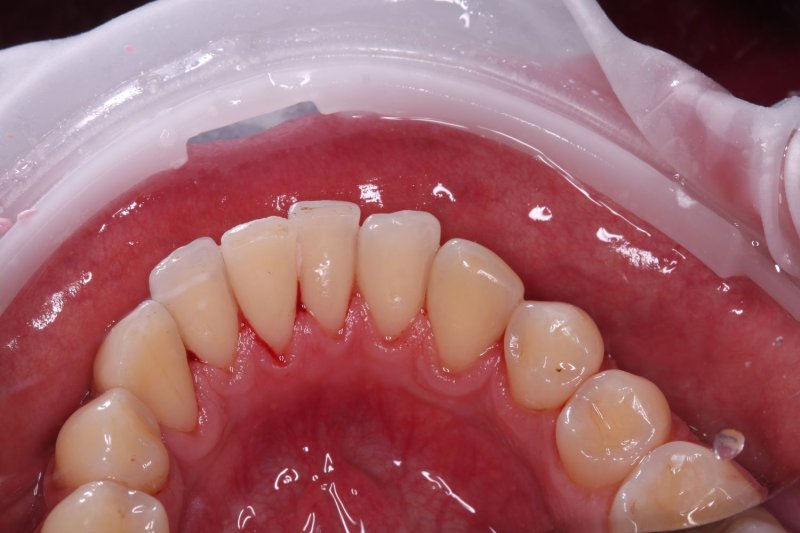

После

udalenie-naleta-ot-kureniya-gbt-posle

Полное удаление всех видов загрязнений: пигментного налета от кофе и сигарет, мягкого бактериального налета и зубного камня. Зубам возвращена природная белизна и гладкость. Свежесть дыхания и здоровый вид десен восстановлены.